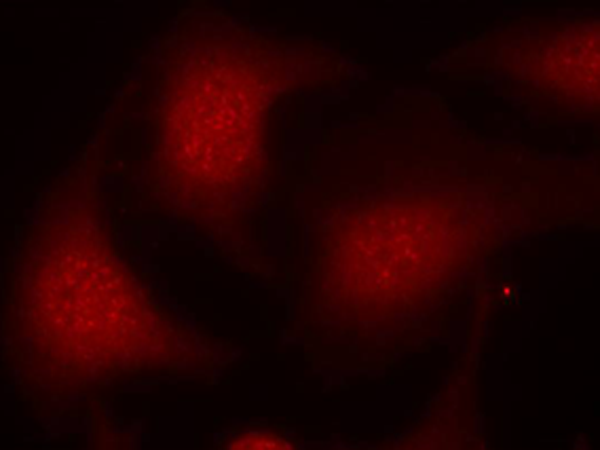

IF Positive control:

Hela cells

IF Recommended dilution

100-200